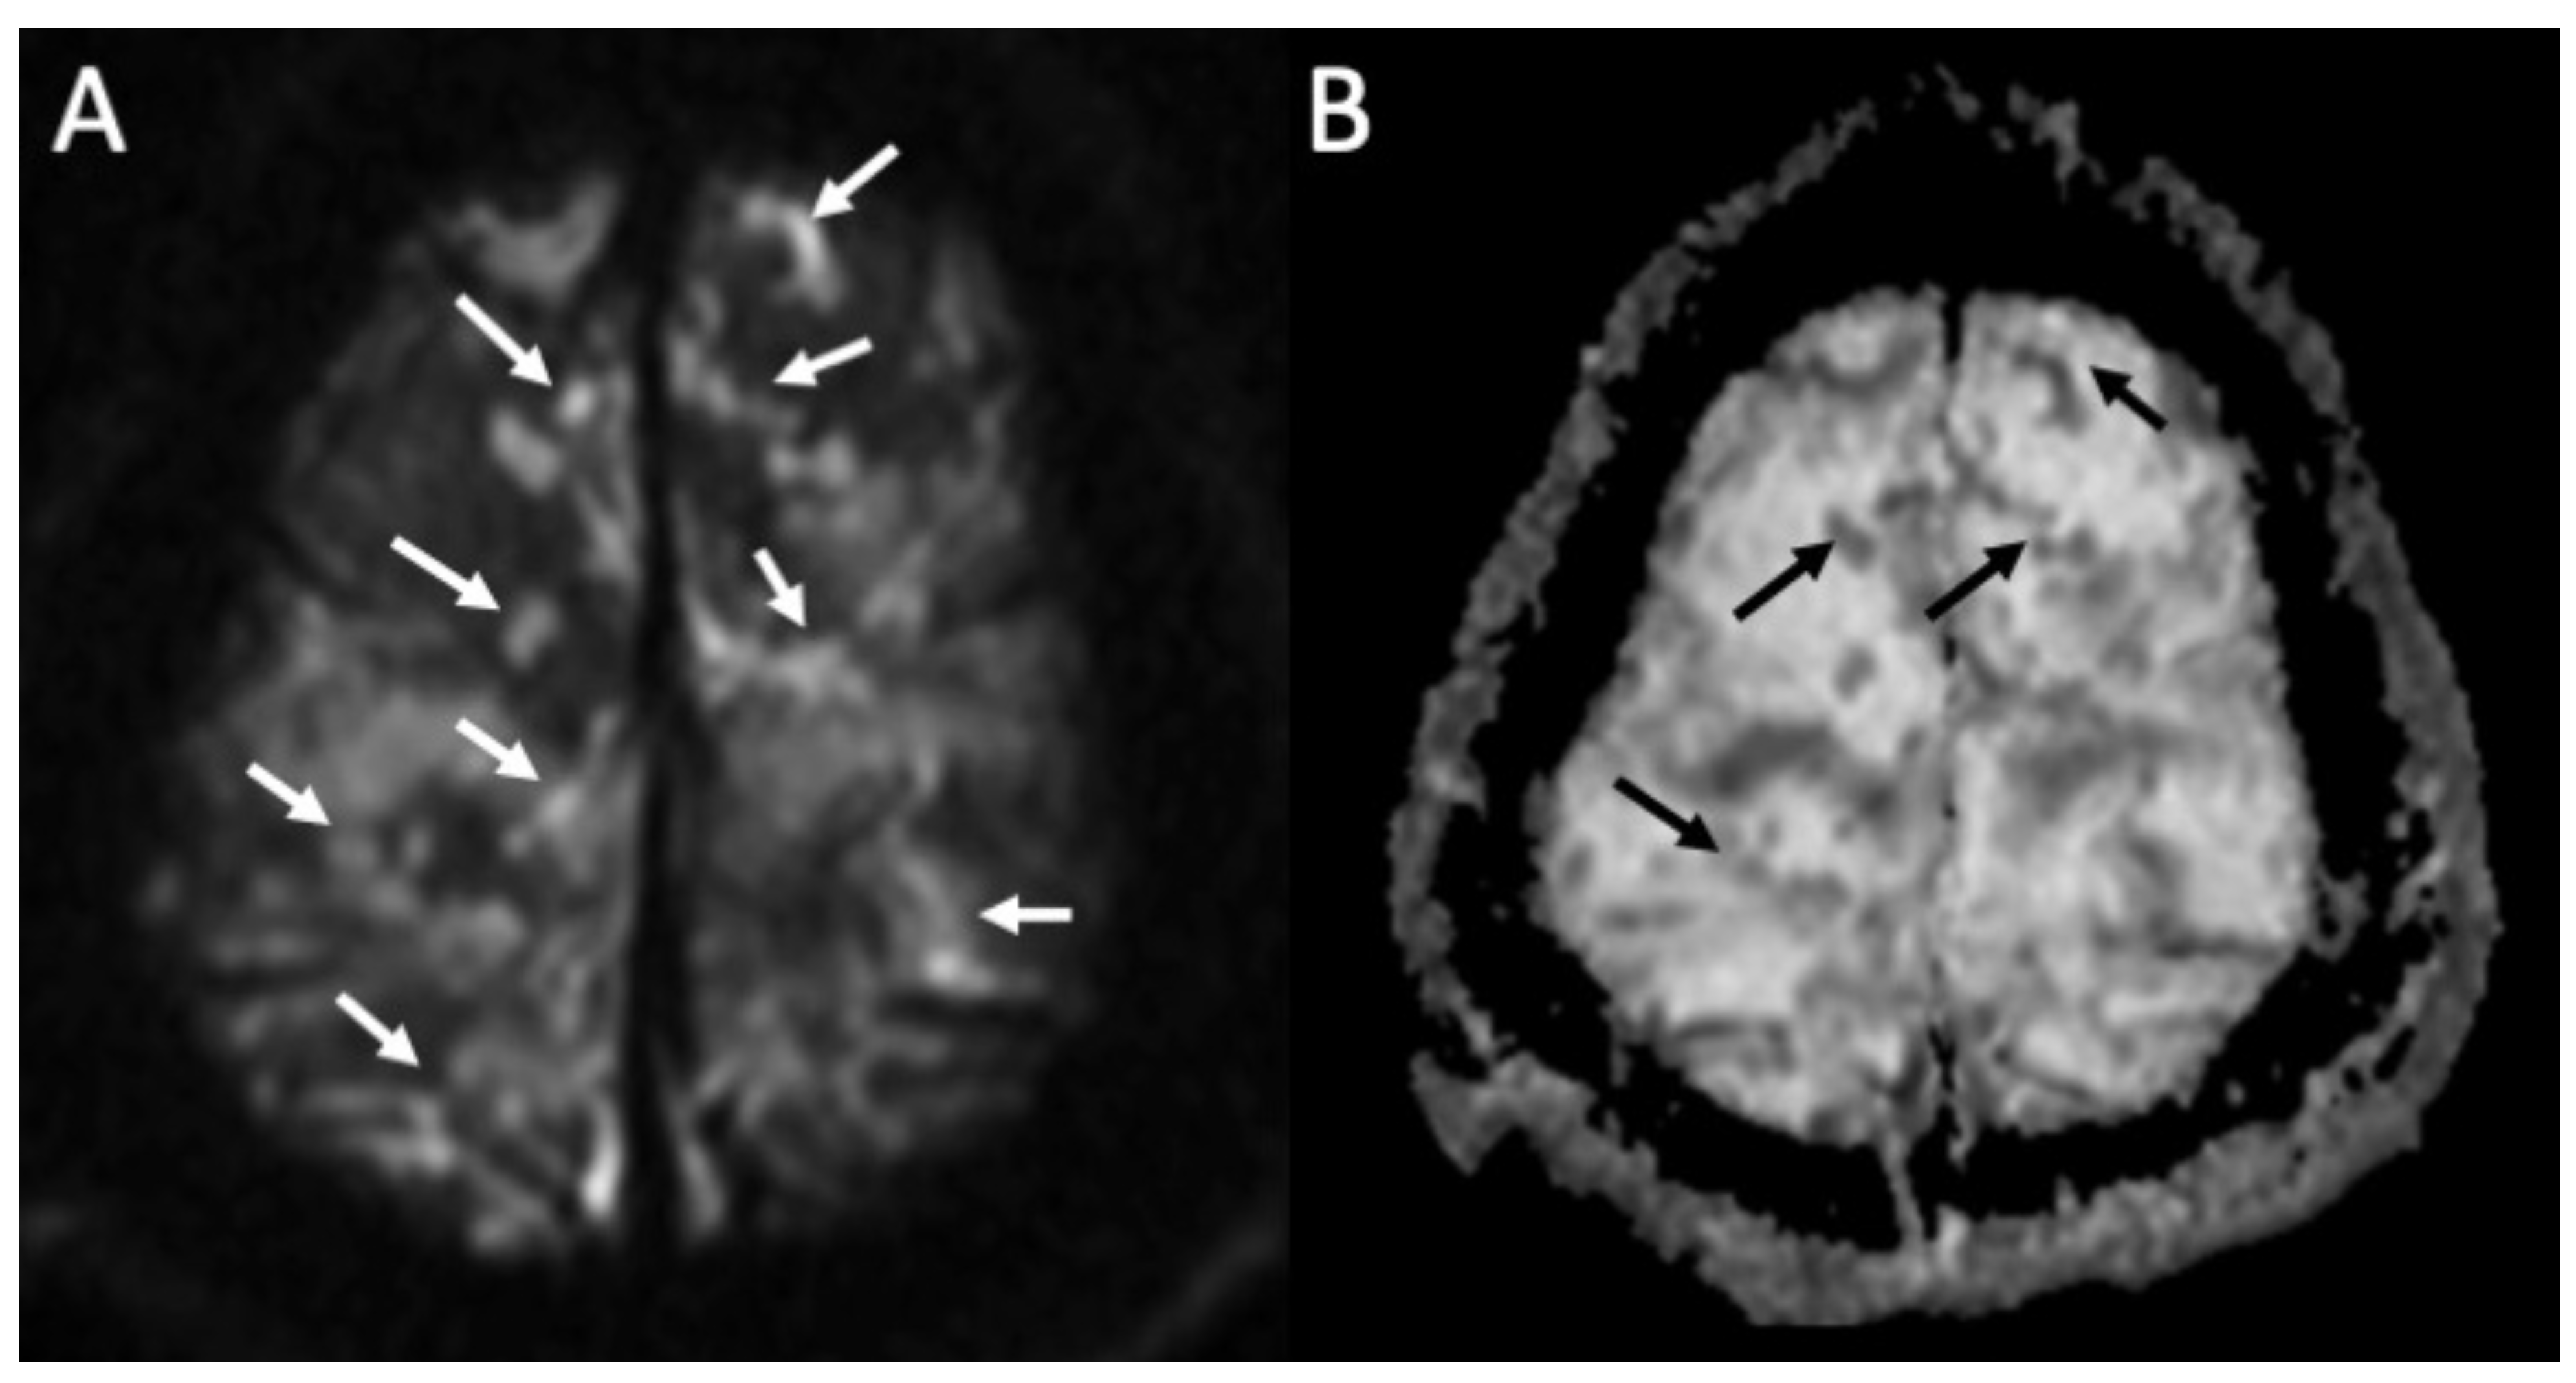

| Piogenic Meningitis | • Cerebrospinal fluid hyperintensity in T1 and FLAIR • Restricted diffusion of the subarachnoid spaces • Meningeal enhancement on T1 and FLAIR |

2. Piogenic Meningitis